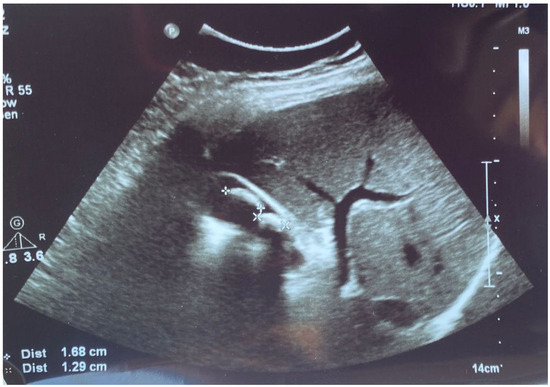

Further, the abdominal and pelvis CT scan with contrast substance showed the cholelithiasis observed on abdominal ultrasound with common bile duct diameter in normal limit values and fused abscess-type collections at the interfibrillar level of the left iliopsoas muscle. The CT also shows hepatomegaly with cranio-caudal dimensions of the right hepatic lobe of 220 mm, a clear, regular outline, a homogeneous structure, and a cholecyst with multiple calculi up to 17 mm (Figure 3).

Figure 3.

Collections of fused abscesses at the interfibrillar level of the left psoas muscle that cause volumetric growth (4.53/4.75 cm) compared to the contralateral side and associate densifications in the adjacent fatty tissue.